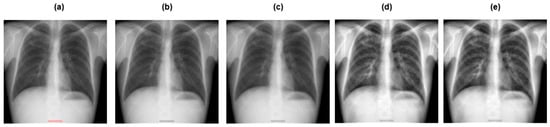

A Lightweight Hybrid Deep Learning Model for Tuberculosis Detection from Chest X-Rays

by Majdi Owda, Ahmad Abumihsan, Amani Yousef Owda and Mobarak Abumohsen

Diagnostics 2025, 15(24), 3216; https://doi.org/10.3390/diagnostics15243216 - 16 Dec 2025

Background/Objectives: Tuberculosis remains a significant global health problem, particularly in resource-limited environments. Its mortality and spread can be considerably decreased by early and precise detection via chest X-ray imaging. This study introduces a novel approach based on hybrid deep learning for Tuberculosis [...] Read more.

Background/Objectives: Tuberculosis remains a significant global health problem, particularly in resource-limited environments. Its mortality and spread can be considerably decreased by early and precise detection via chest X-ray imaging. This study introduces a novel approach based on hybrid deep learning for Tuberculosis detection from chest X-ray images. Methods: The introduced approach combines GhostNet, a lightweight convolutional neural network tuned for computational efficiency, and MobileViT, a transformer-based model that can capture both local spatial patterns and global contextual dependencies. Through such integration, the model attains a balanced trade-off between classification accuracy and computational efficiency. The architecture employs feature fusion, where spatial features from GhostNet and contextual representations from MobileViT are globally pooled and concatenated, which allows the model to learn discriminative and robust feature representations. Results: The suggested model was assessed on two publicly available chest X-ray datasets and contrasted against several cutting-edge convolutional neural network architectures. Findings showed that the introduced hybrid model surpasses individual baselines, attaining 99.52% accuracy on dataset 1 and 99.17% on dataset 2, while keeping low computational cost (7.73M parameters, 282.11M Floating Point Operations). Conclusions: These outcomes verify the efficacy of feature-level fusion between a convolutional neural network and transformer branches, allowing robust tuberculosis detection with low inference overhead. The model is ideal for clinical deployment and resource-constrained contexts due to its high accuracy and lightweight design. Full article